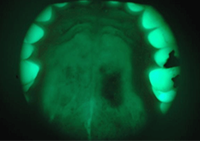

What is VELscope Vx?

- The VELscope Vx helps discover oral disease BEFORE it can be seen under ordinary light

- The VELscope Vx exam is quick, painless, and effective

- The Velscope Vx offers the early discovery of oral diseases, including precancer and cancer.